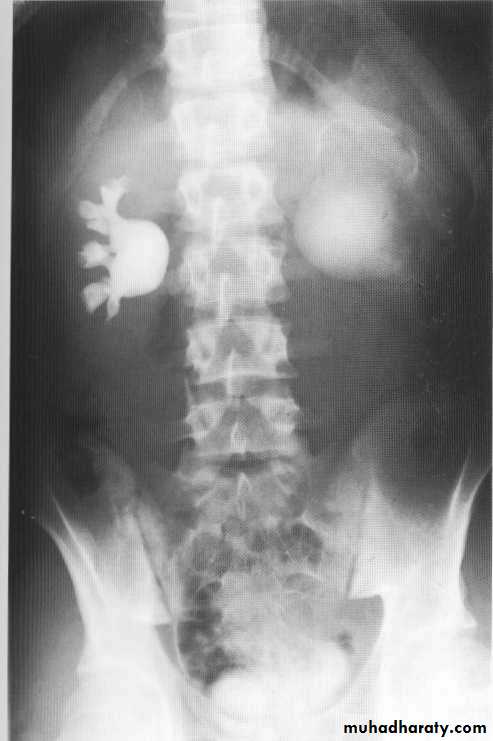

Pelviureteric junction obstruction

This condition has a spectrumof severity from severe antenatal hydronephrosis with global cortical loss to radiologically demonstrable hydronephrosis in theadult without apparent symptoms or loss of renal functionUp to 20%are associated with an accessory renal artery running across thePUJ, which may be visible on the IVU as a smooth indentation.

During the acute episode there are features on IVU of severe acute obstruction, which include a delayed, increasingly dense nephrogram and delayed appearance (sometimes up to 24 h or more) of contrast within the collecting system. When opacification occurs it demonstrates clubbed calyces and a dilated pelvis